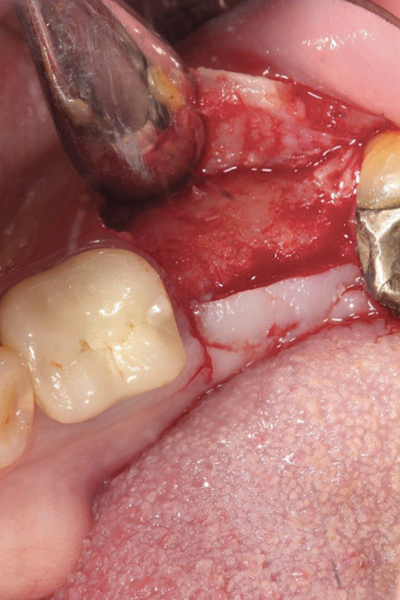

Fig 4. d-PTFE barrier in position on the lingual; it will be tucked under the flap on the buccal.

Figure 4

Fig 5. Bone graft placed in the socket.

Figure 5